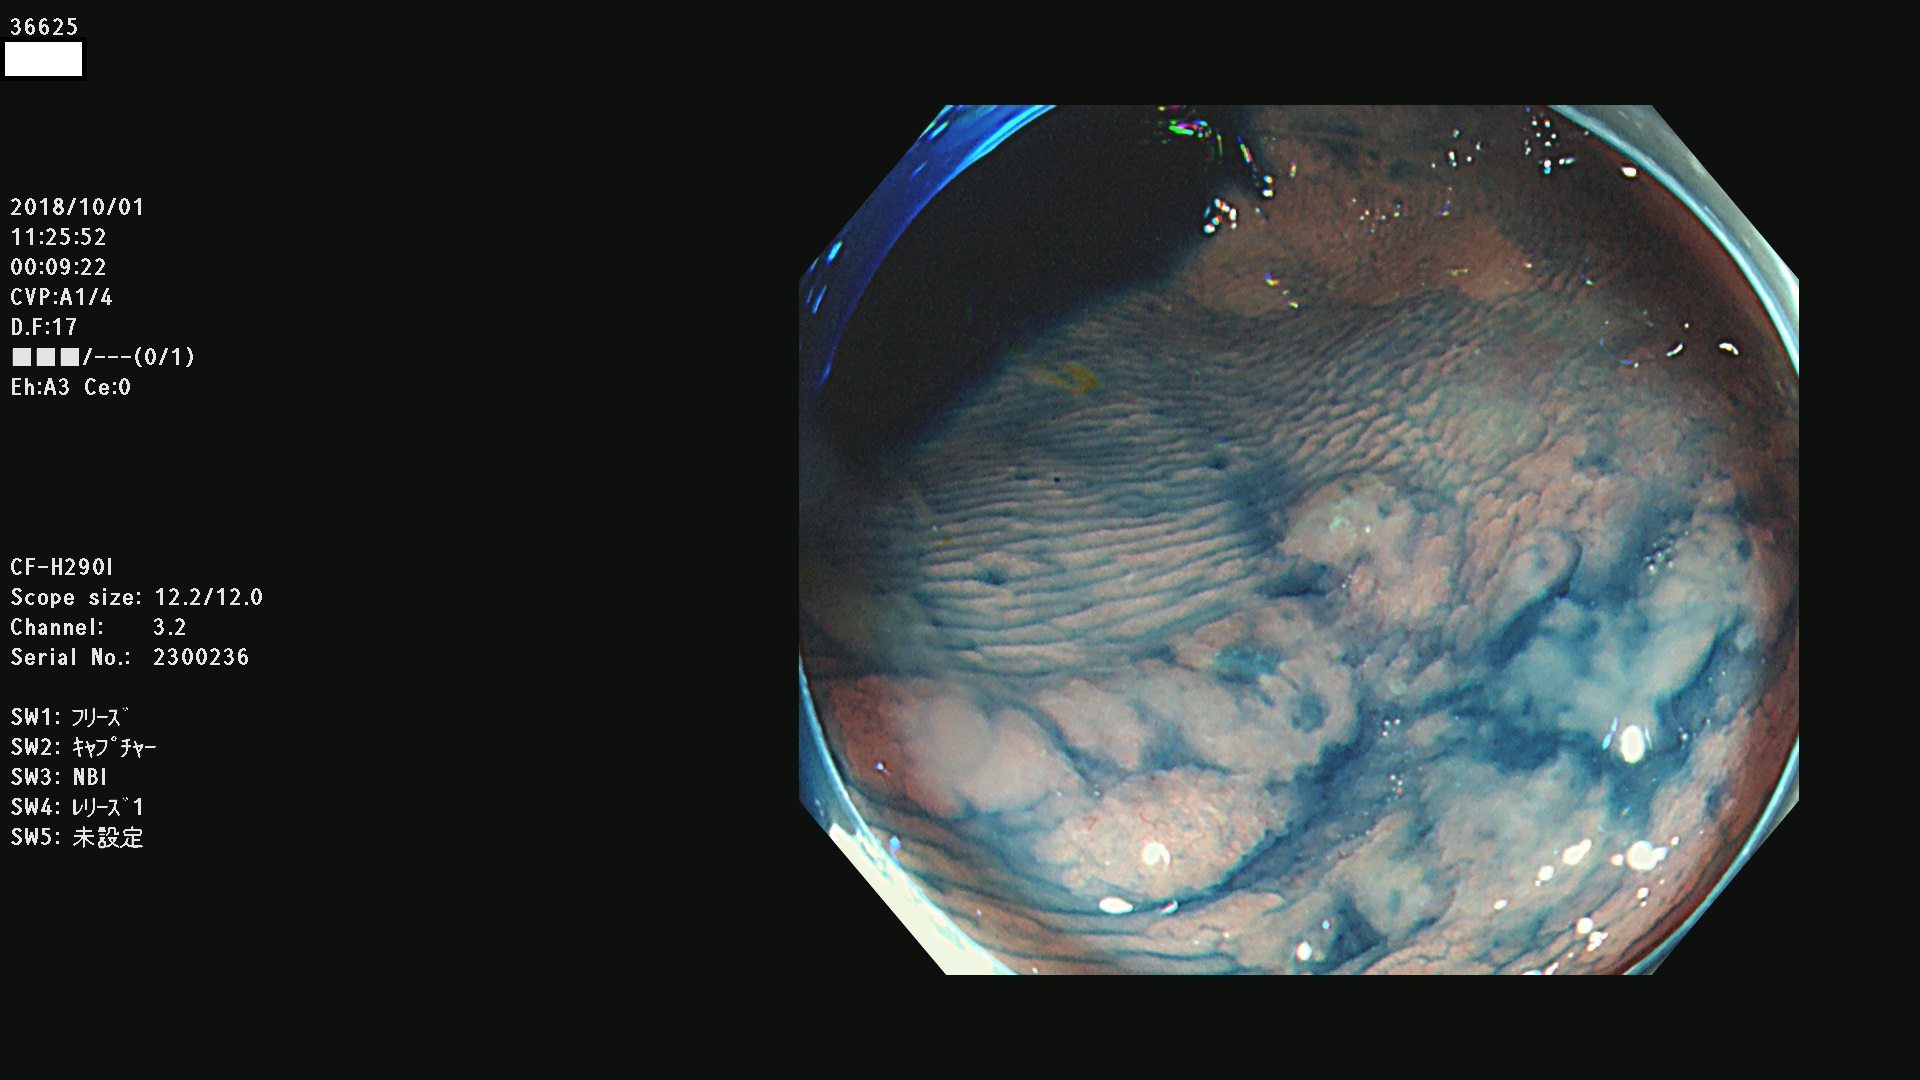

36600 36601 36603 36605 36606 36608 36609 36610 36611 36612 36613 36615 36617 36620 36621 36624 36625 36626 36627 36628 36629 36631(SSAPのみ) 36632 36633 36634 36636(SSAPのみ) 36637(SSAPのみ) 36639 36640 36642 36643 36644 36646 36647 36648 36649(SSAPのみ) 36650(SSAPのみ) 36652 36653 36654 36655(SSAPのみ) 36656 36657 36658 36659 36660 36661(SSAPのみ) 36665 36668 36669 36672 36673 36676 36677 36678 36679 36681 36682 36683 36684 36685 36687(SSAPのみ) 36691 36692 36693 36694 36695 36696 36697 36699(SSAPのみ)

発見困難で危険性の高い平坦型病変(上記100名より抽出)